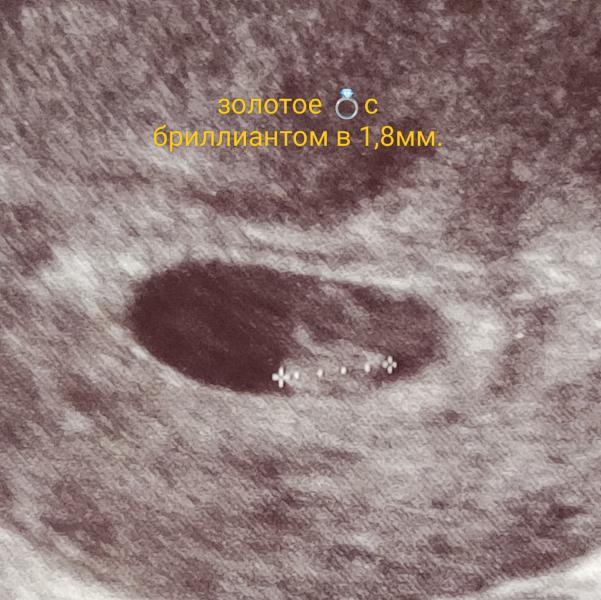

УЗИ прошла, сказали можно вставать на учет по беременности! Какие документы нужны?

Узи прошла, сказали можно вставать на учёт.